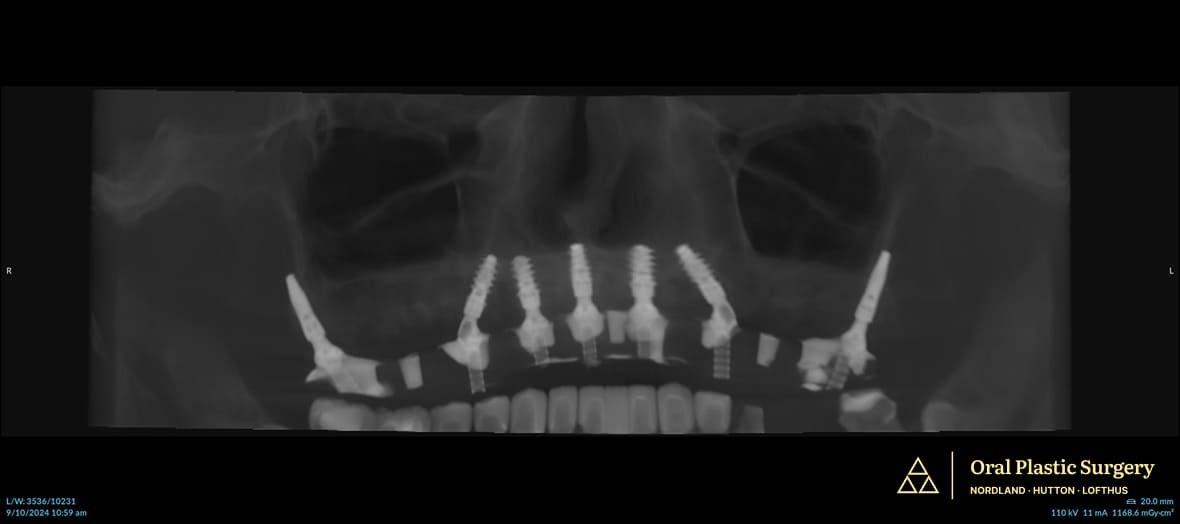

- Surgical Execution: Placement of seven implants, including two pterygoid implants in the posterior maxilla (base of the skull). This enabled full restoration of all 14 upper teeth, including molars.

This approach minimized cantilevers (overhangs), improved durability, and delivered the long-term stability and function Phil needed.

Post-surgery X-ray shows all seven implants in place. The pterygoid implants provide secure anchorage in the upper jaw, allowing Phil to regain molars and full chewing strength.

Surgical view: seven implants, including two pterygoid implants, were placed for maximum stability and function. Precise implant placement improved chewing strength and long-term durability.

All seven implants, including the two pterygoids, achieved excellent stability. The full-arch restoration restored complete function with uneventful healing.